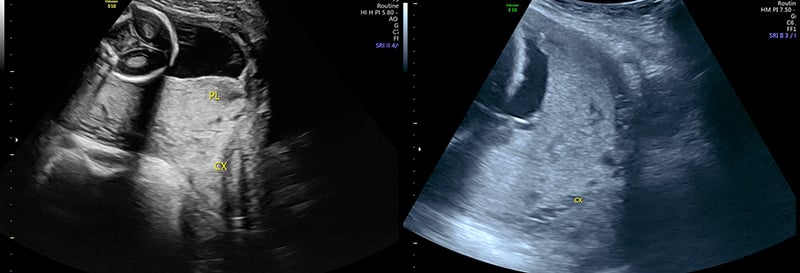

- Placentation

- Abnormal placentation such as placenta previa increases the risk of peripartum maternal hemorrhage.27

- Detecting abnormal placentation prior to delivery may allow preparation for increased hemorrhage or operative delivery and lower risk to the mother.

- Placenta previa (covering the internal cervical os) or low-lying placenta (within 2 cm but not covering the cervical os) should be confirmed by transvaginal US if available.

Figure 35. Sagittal transabdominal view of the pelvis revealing the anechoic urinary bladder (BL) and a normal cervix (CX) just below.

Figure 36. Sagittal transabdominal view of the pelvis similar to Figure (prior), with hyperechoic placenta (PL) covering the internal cervical os (CX).